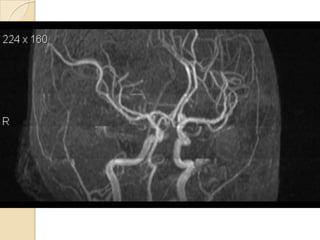

NORMAL MRA

Arteries of the brain (cranial view) - MRA

1. Anterior cerebral artery

2. Anterior communicating artery

3. Basilar artery

4. branches (in insula) of middle

cerebral artery

5. Cavernous portion of internal

carotid artery

6. Cervical portion of internal carotid

artery

7. Genu of middle cerebral artery

8. Intracranial (supraclinoid) internal

9. Middle cerebral artery

10. Ophthalmic artery

11. Petrous portion of internal carotid

12. Posterior cerebral artery

13. Posterior cerebral artery in ambient

cistern

14. posterior cerebral artery in

interpeduncular cistern

15. Posterior communicating artery

16. Posterior inf cerebellar artery.

17. Quadrigeminal portion of posterior

18. Superior cerebellar artery

19. Vertebral artery